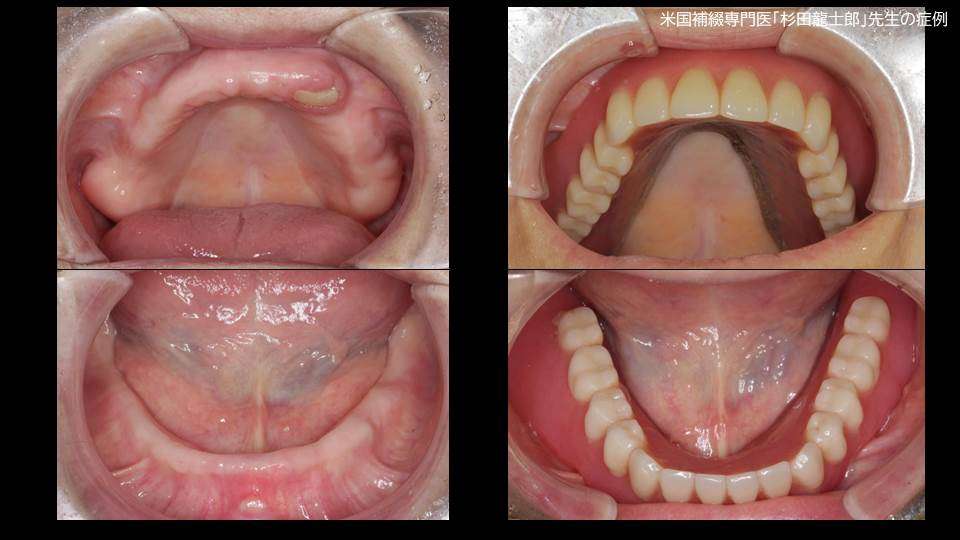

写真の義歯は、総入れ歯の上アゴ部分を覆っているピンクのプラスチックがどうしても違和感が強く、食事の時と外出する時以外は入れ歯を装着出来ていない状態で、通っているお医者さんからの紹介を受けて当院に受診された患者様です。

上顎は「無口蓋型金属床総義歯」で治療をしました。装着して2年目に入られた患者様の例ですが、健康保険適用の入れ歯とは違い、一度得られた歯並び、咬み合わせ、安定感には変化がありません

※画像の治療は米国補綴専門医 兼 歯周病専門医」の杉田龍士郎先生の治療です。

●上顎:無口蓋型 金属床 総義歯 約50万円